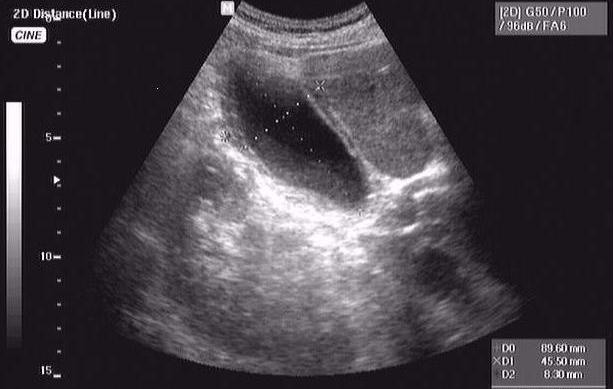

76 летний пациент - конкремент желчного протока, печень правая - 178 мм, левая - 62 мм

сахарного диабета нет, зато есть уртикарная сыпь... шистосомоз?

Онищук76 33.JPG

Онищук76 44.JPG

Онищук76 11.JPG